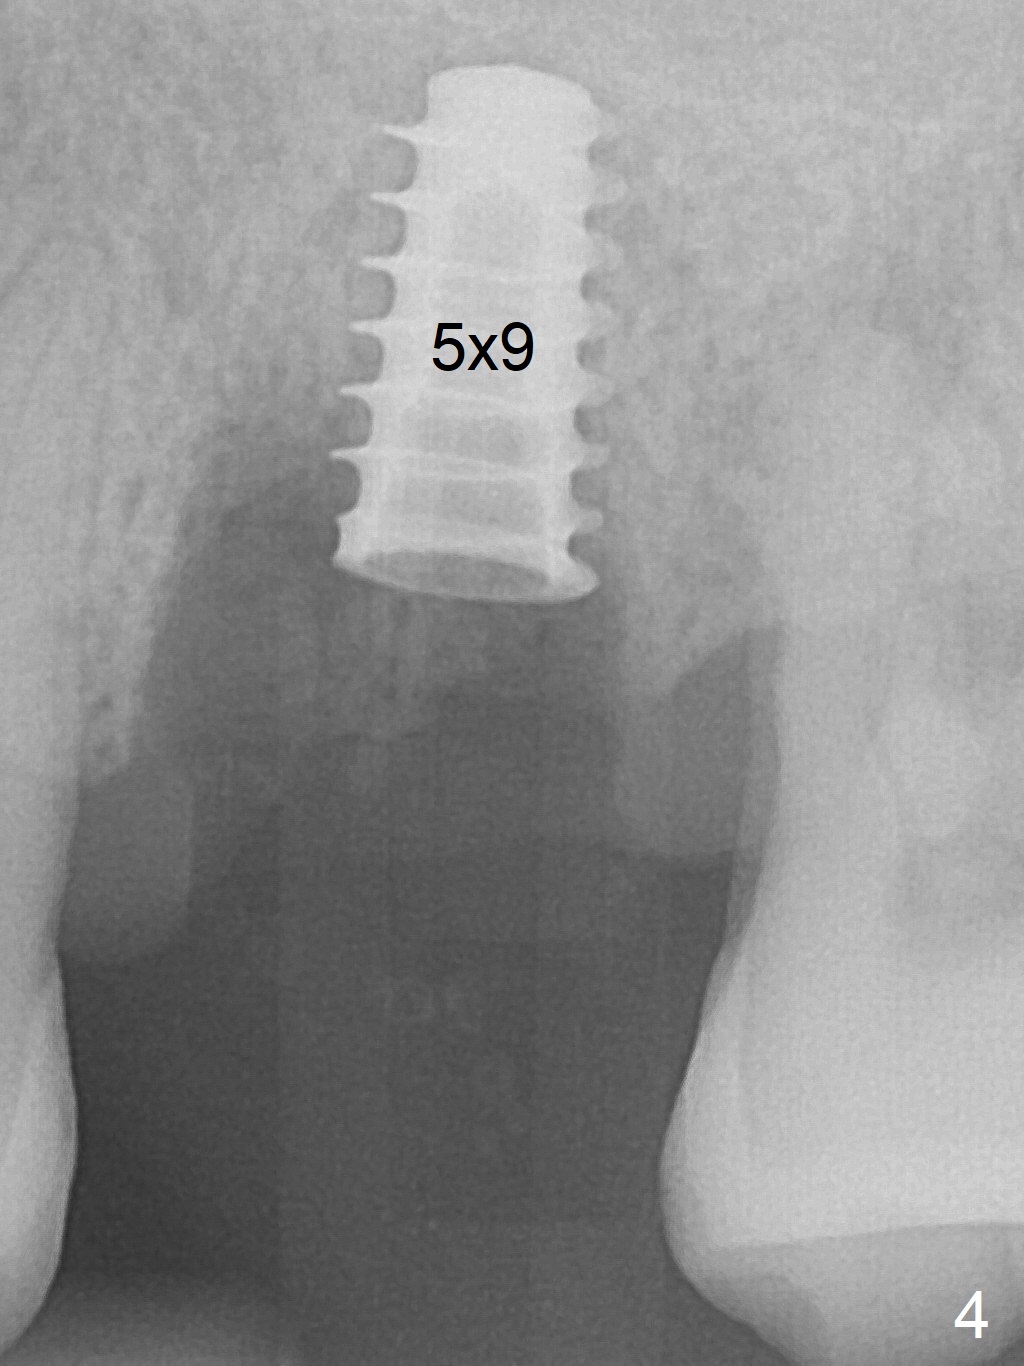

The ridge over the mobile tooth #14 is wide, suggesting bruxism pathogenesis (Fig.1). In spite of calculus over the roots of the extracted tooth (Fig.2), the septum remains. Osteotomy is initiated in the palatal slope of the septum (Fig.3,3' red dashed line). A 4.3 mm Magic Drill (MD) cannot bite into the bone probably because of the slope. Sequential osteotomy has to be done, starting with the smallest MD until 4.8 mm one. A 5x9 mm dummy implant is placed with 50 Ncm (Fig.4). To place 5x11 mm IBS implant (Fig.5), 5.3 mm MD has to be used; prior to implant placement, sinus lift is accomplished with mixture of autogenous bone and Vanilla graft (white *); more allograft (black *) is placed around the implant before insertion of a 6x5.7(3) mm abutment. More allograft is placed around the abutment (Fig.6 *) prior to an immediate provisional fabrication. The grafted bone appears to become the native bone, although at the low density, 6.5 months postop (Fig.7). The implant at #14 appears to have been placed in the middle of the alveolus buccopalatally (Fig.8).